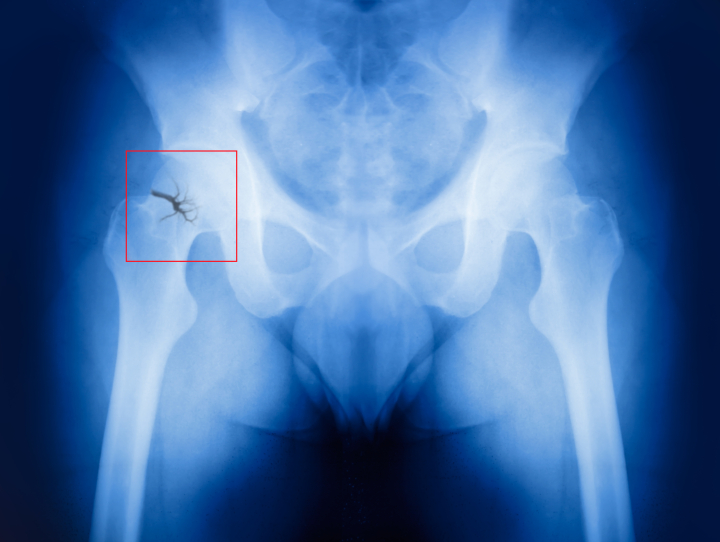

Platelet-rich plasma application during cesarean delivery can prevent wound complications by promoting speedy recovery and reduced reliance on pain medications after surgery.

The use of Platelet-rich plasma (PRP) microinjection during cesarean section could enhance wound healing and alleviate the need for analgesics/pain killers, found a study issued in the Medicina (Kaunas).

Results indicated that the application of PRP remarkably improved surgical wound healing. Scar quality was evaluated using the patient-recorded POSAS score (Patient and Observer Scar Assessment Scale) at different time points post-surgery. Notably, no cases of dehiscence were reported in either group. Although there were no significant differences in postoperative pain intensity (as assessed by the visual analogue scale), the women who were treated with PRP presented reduced analgesic needs (lesser daily paracetamol doses) than the control group.